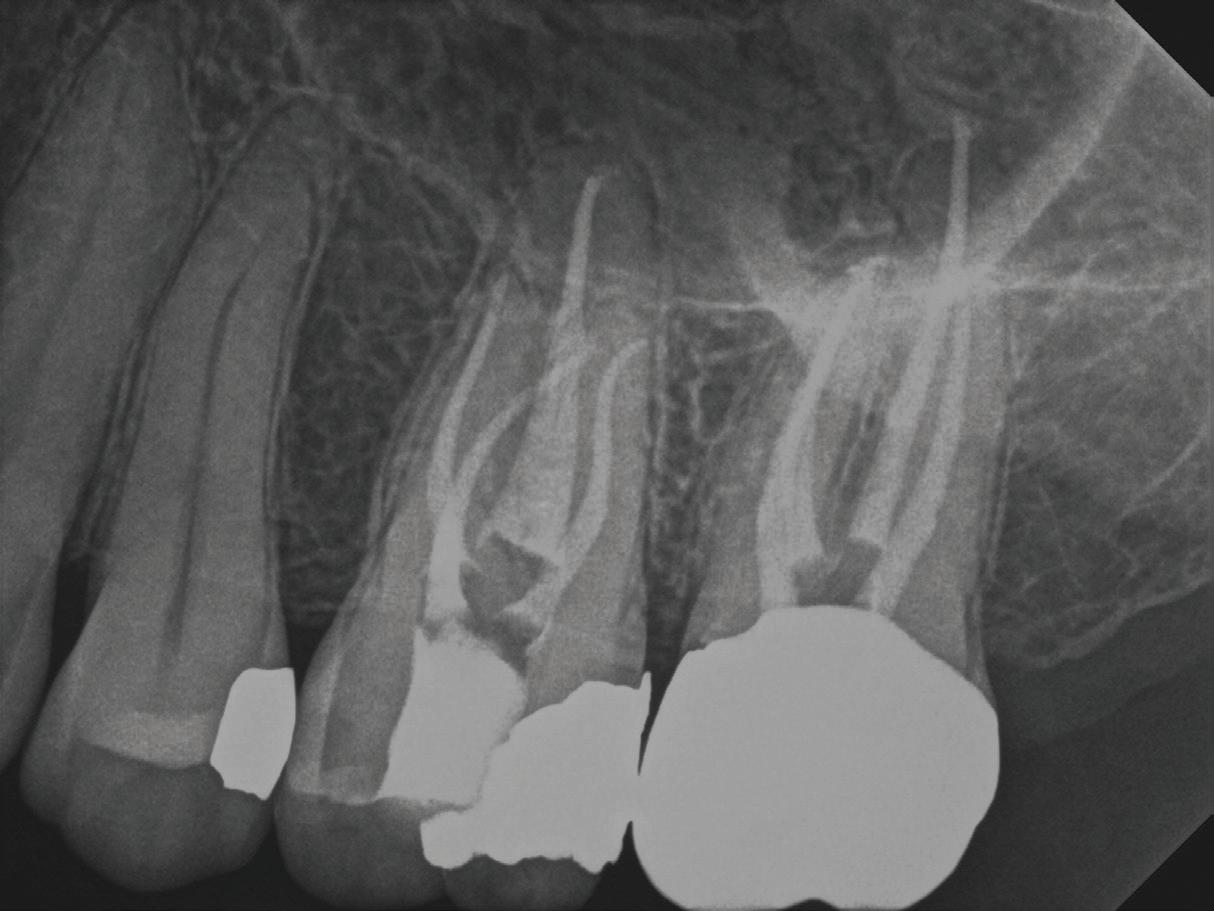

A periapical radiograph and a limitedfield-of-view cone beam computed tomogram of teeth 14 and 15 were taken, and no radiographic signs of apical periodontitis related to these teeth were noted that day (Fig 1). Sensibility tests were also performed. Tooth 15 responded normally to palpation and to bite and felt “different” on percussion (not painful, which is an important distinction to make). Tooth 14 responded

normally to palpation, percussion, and bite. Cold placed on tooth 14 triggered a significantly elevated, throbbing response that lingered more than 1 minute. Of all the tests performed, the cold on tooth 14 most closely replicated the pain of her chief complaint.

At our final appointment, I was able to fully instrument the MB1 canal. The final postoperative radiograph shows the curvature of the MB1 canal of tooth 14 (Fig 2). The teeth were closed with a medicated sponge and provisional material, and the patient was referred back to her general dentist for restoration of these teeth.

Fig 2. Postoperative radiograph of teeth 14 and 15.

Fig 1. Preoperative radiographs. A. Tooth 14. B. Tooth 15.